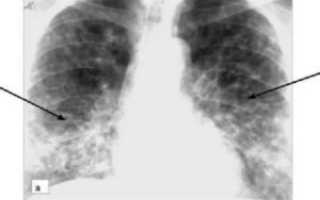

Двусторонняя нижнедолевая пневмония

Больной направляется на рентген, который покажет локализацию воспалительных очагов в виде затемнения и усиления легочного рисунка, а также вероятные осложнения (абсцесс, плеврит и другие). В особых случаях используют спиральную компьютерную томографию (детям противопоказано). Кроме этого, назначают анализы крови, мочи и бактериологическое исследование мокроты.